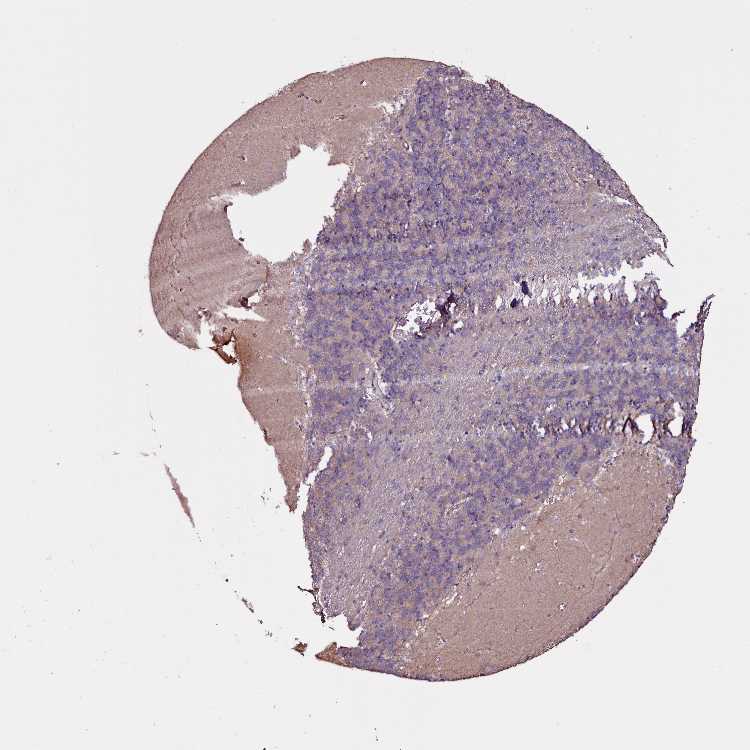

BRAIN CEREBELLUM Show tissue menu

CEREBELLUM - Antibody stainingi

Antibody staining in the annotated cell types in the current human tissue is reported as not detected, low, medium, or high, based on conventional immunohistochemistry profiling in selected tissues. This score is based on the combination of the staining intensity and fraction of stained cells.

Each image is clickable and will lead to virtual microscopy that enables deeper exploration of all samples and also displays staining intensity scores, fraction scores and subcellular localization as well as patient and tissue information for each sample.

Antibody HPA040603

Purkinje cells Low

Cells in granular layer Low

Cells in molecular layer Not detected